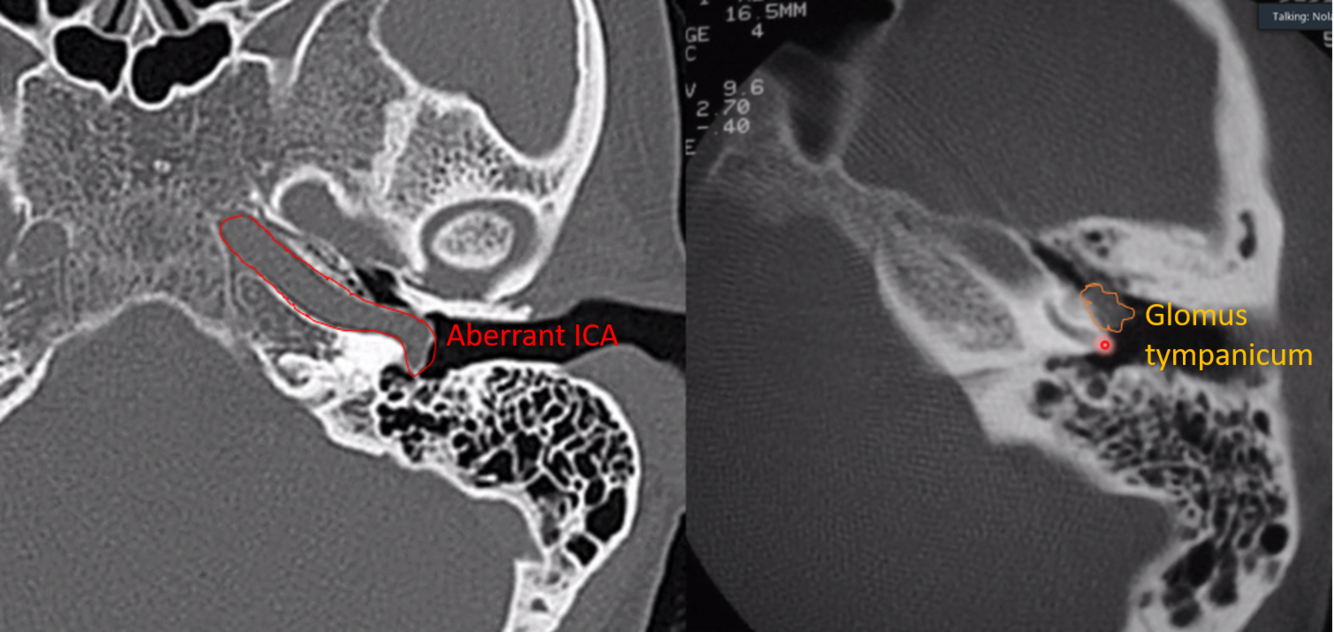

aberrant ICA

carotid > jugulare > tympanicum > vagale

what are each of these entities (they are different cases)